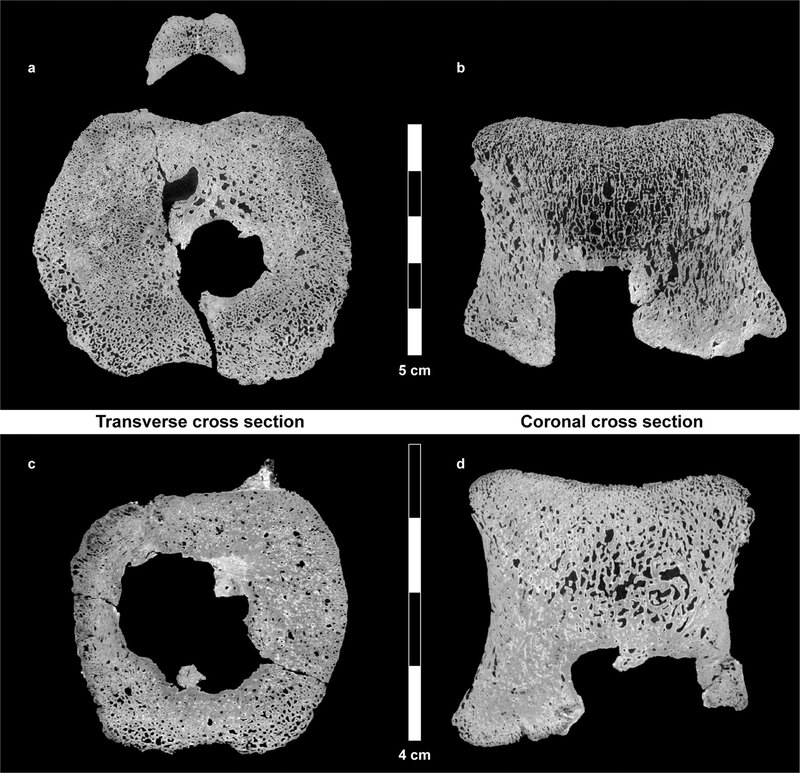

На восьми из одиннадцати найденных позвонков были видны следы, которые заинтересовали эволюционных анатомов и палеонтологов. Исследователи заподозрили рак и не ошиблись. Компьютерная томография костей с разрешением в несколько микрометров позволила построить трехмерную модель тканей, а также реконструировать опухоль со всеми прилегающими сосудами. По всем признакам перед учеными был гистиоцитоз X, только возрастом более 60 миллионов лет.